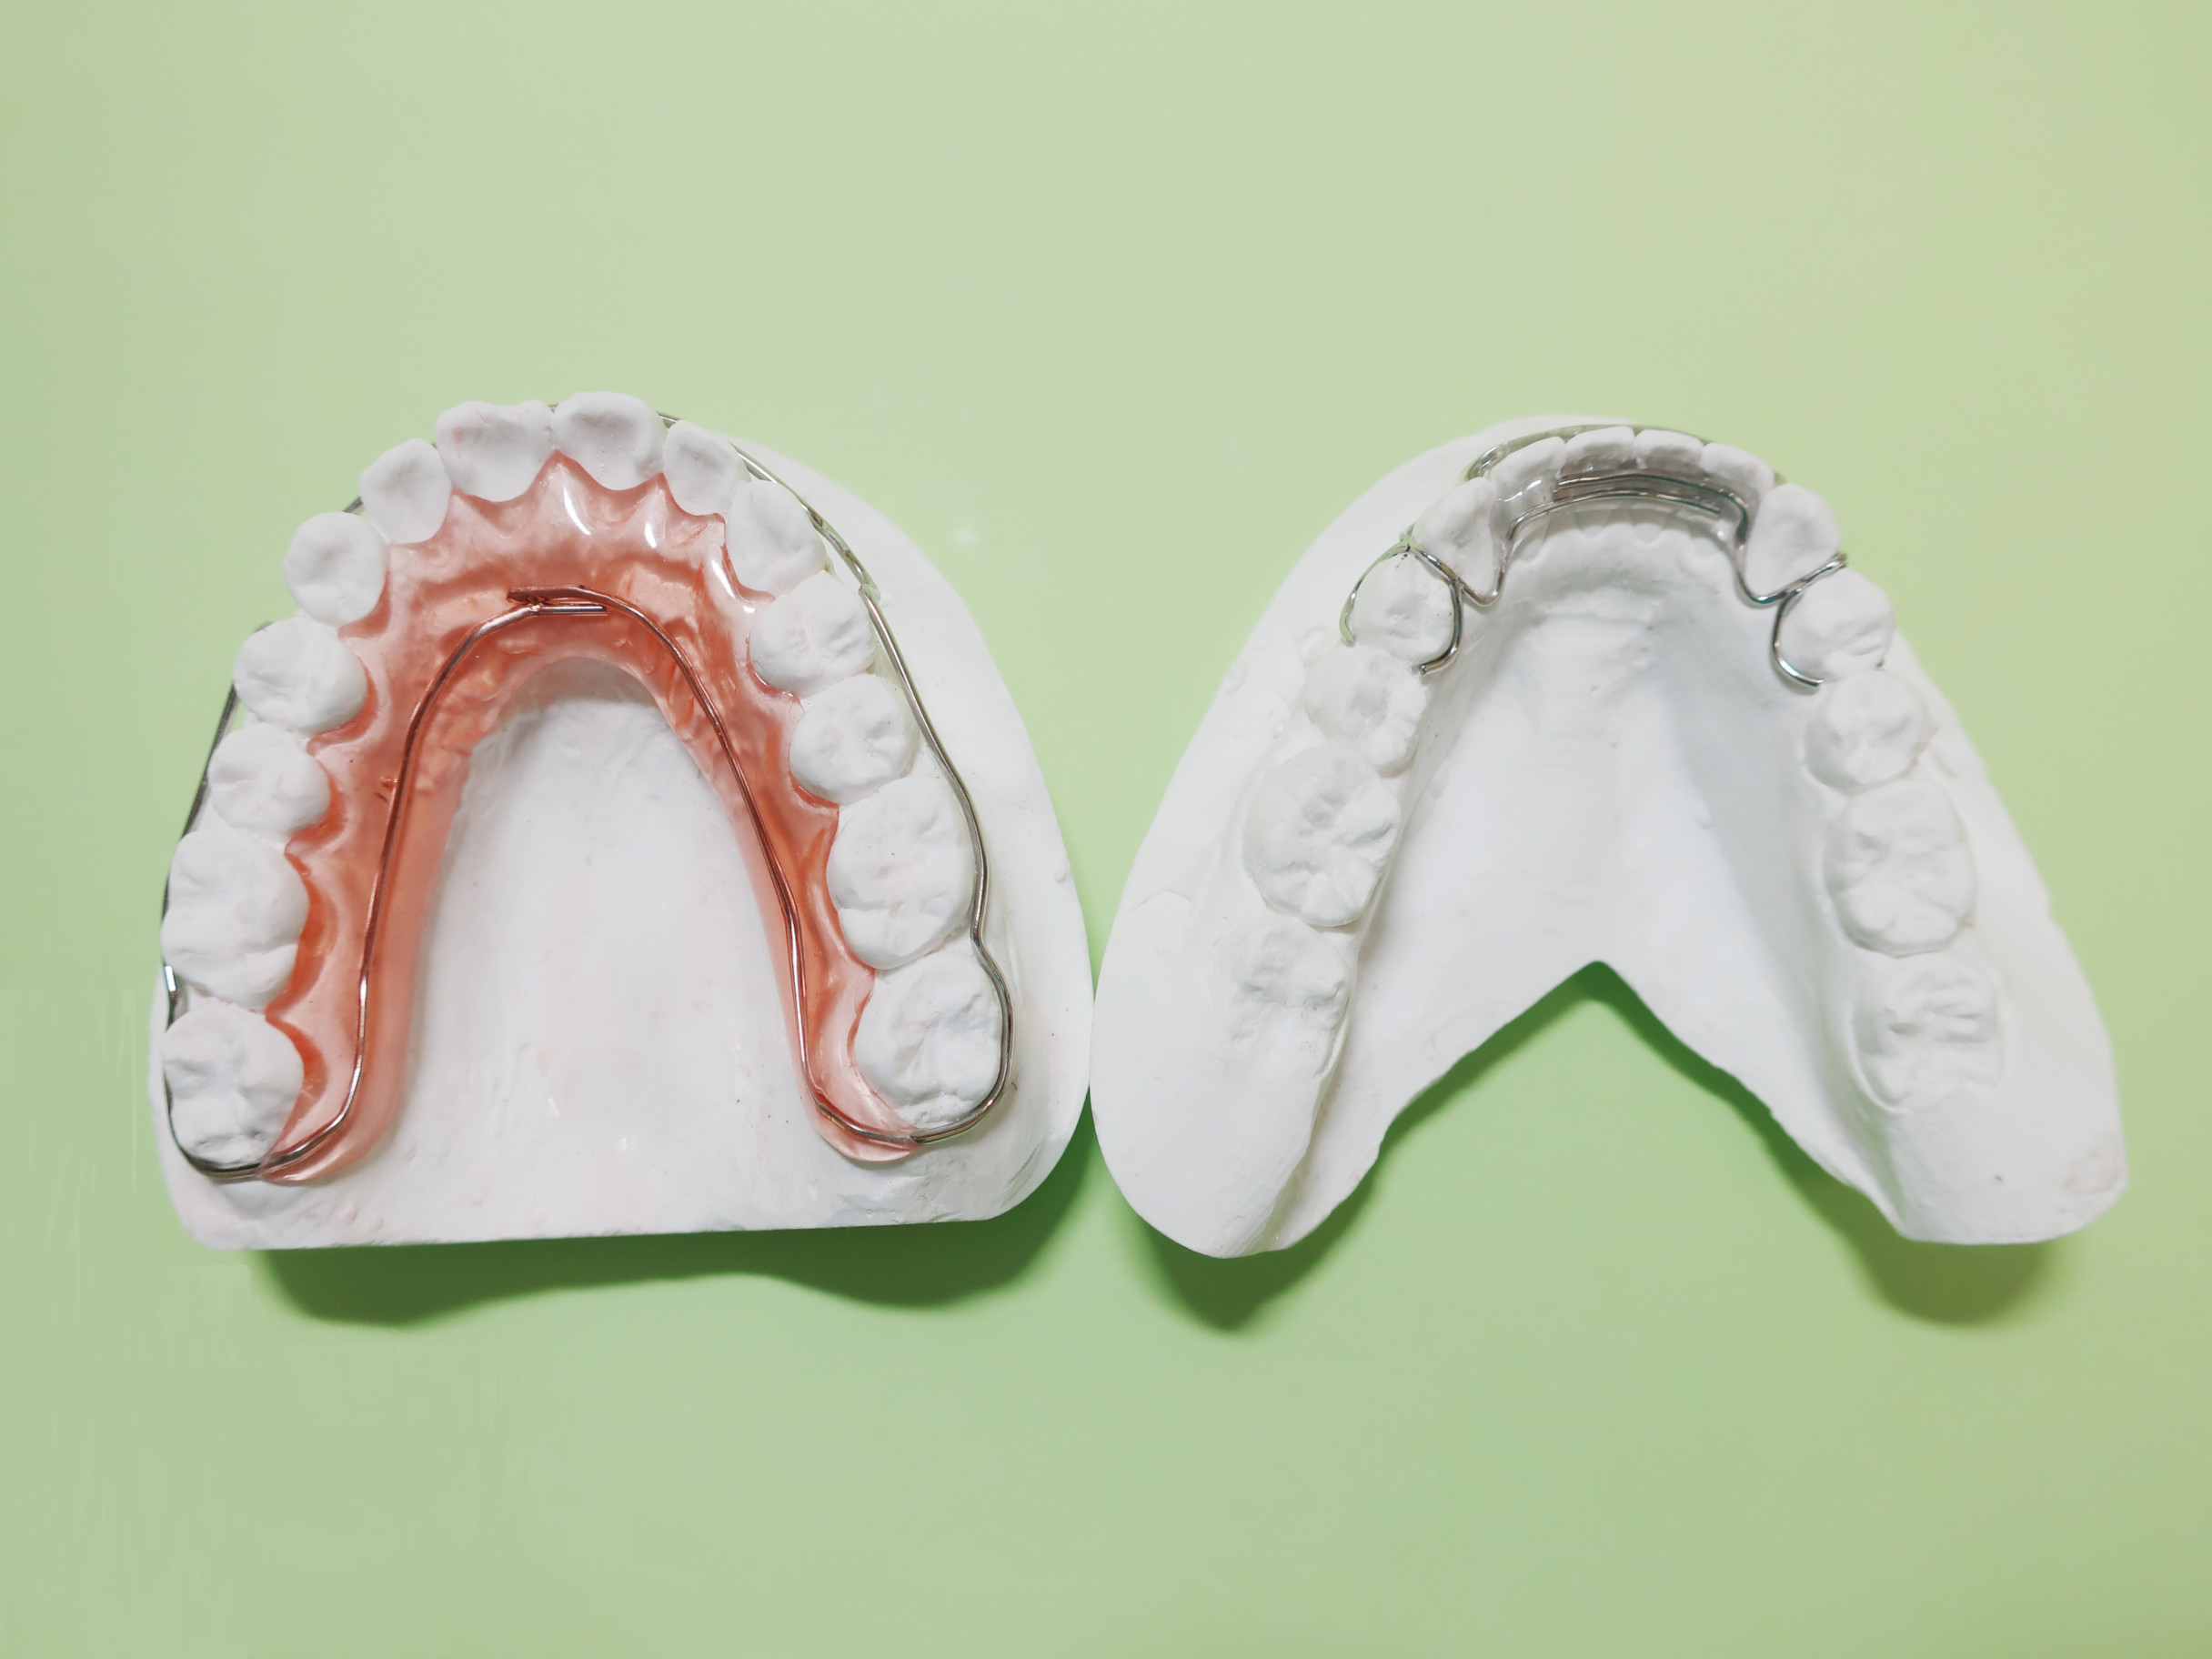

⑤保定期間

移動を終えた後もしばらくの間、歯は元に戻ろうとする性質があります。そこで、食事の時などには取り外すことができる保定装置を使い、移動した歯をしっかり安定させます。その間に3~6ヵ月に1回程度、およそ2年間の通院をおすすめしています